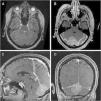

To report a case of post-surgical encephalocele through craniotomy burr holes following the resection of a meningioma of the posterior fossa. A 49-year-old female presented in the emergency room with cephalea. The MRI showed a meningioma of the convexity of the posterior fossa. A resection was performed and the bone flap replaced. The patient recovered uneventfully and was discharged. After 30 days the patient consulted referring cephalea, vomiting and imbalance. Brain MRI revealed a trans-cranial cerebellar herniation through the craniotomy burr holes. An urgent surgery was performed to repair the encephalocele. Post-surgical brain MRI was performed and did not show complications.

Post-surgical encephalocele is an uncommon complication after the resection of a posterior fossa lesion. To avoid this complication, it is recommended thorough dural and bony closure, particularly in the posterior fossa surgeries and in high-risk patients.